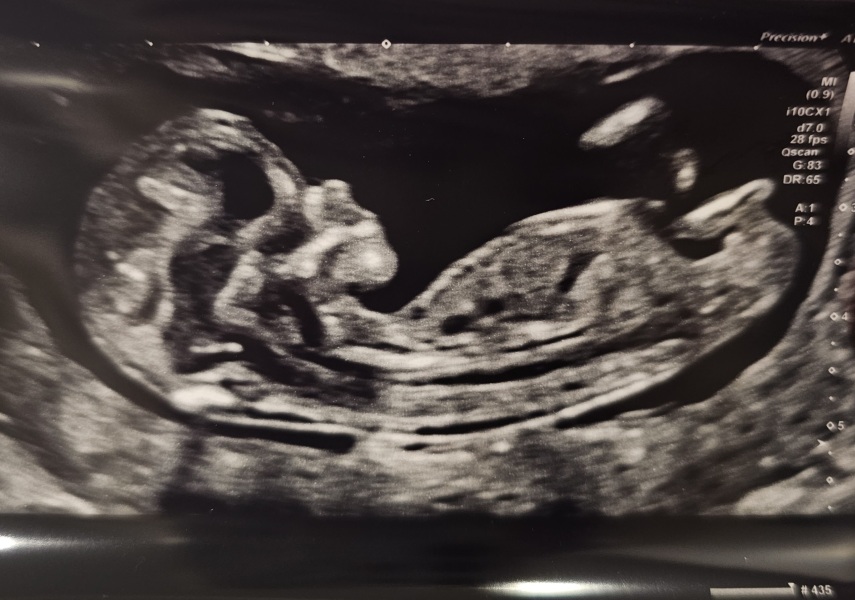

rupertbear91 · 15/03/2024 14:40

I survived the long morning wait! Baby took 10 minutes to stop standing on its head but behaved in the end and all looking good. So relieved!

Trying to guess nub theory but I am clueless 😂